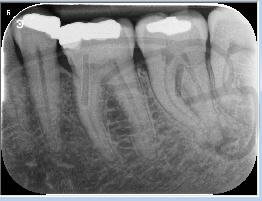

There are a number of ways to decide whether you need root canal treatment and the specific x-rays, scans and tests help diagnose your problem.An important sign is the type of pain you have been having with a tooth. It helps me decide if a tooth is in need of treatment and even if it saveable.

I really enjoy undertaking root canal treatments - rising to the challenge and helping people out of dental pain for the long term.I was privileged to be asked to speak at the 2016 BDA Conference, where I have a lecture about providing quality endodontic outcomes to patients, working as a generalist. Avoiding problems and pitfalls and maximising efficiency. One of the main matters that he covered was understanding that what is seen on plane radiography is utterly misleading and should not be the criteria by which a generalist continues treatment once it has been started.

At the 2016 BDA Conference, Thomas spoke about providing quality endodontic outcomes to patients, working as a generalist. Avoiding problems and pitfalls and maximising efficiency. One of the main matters that he covered was understanding that what is seen on plane radiography is utterly misleading and should not be the criteria by which a generalist continues treatment once it has been

started.